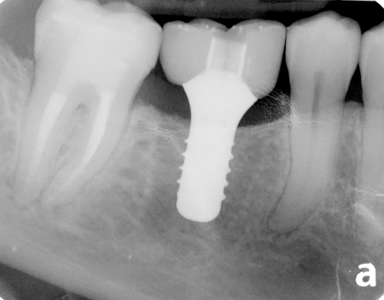

另外,如果你口腔有植牙,建議使用牙縫刷。因為植牙一般頸部比原來真牙窄,另外亦考慮一些膠質或有膠包著的(coated plastic core wire),可避免劃花植牙而令牙菌膜積聚。

植牙一般頸部比原來真牙窄